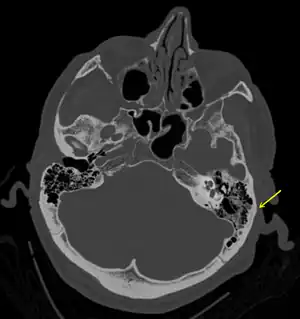

| Basilar skull fracture | |

| A subtle temporal bone fracture as seen on a CT scan | |

Temporal bone fractures

Acute injury to the internal carotid artery (carotid dissection, occlusion, pseudoaneurysm formation) may be asymptomatic or result in life-threatening bleeding. They are almost exclusively observed when the carotid canal is fractured, although only a minority of carotid canal fractures result in vascular injury. Involvement of the petrous segment of the carotid canal is associated with a relatively high incidence of carotid injury.[9]